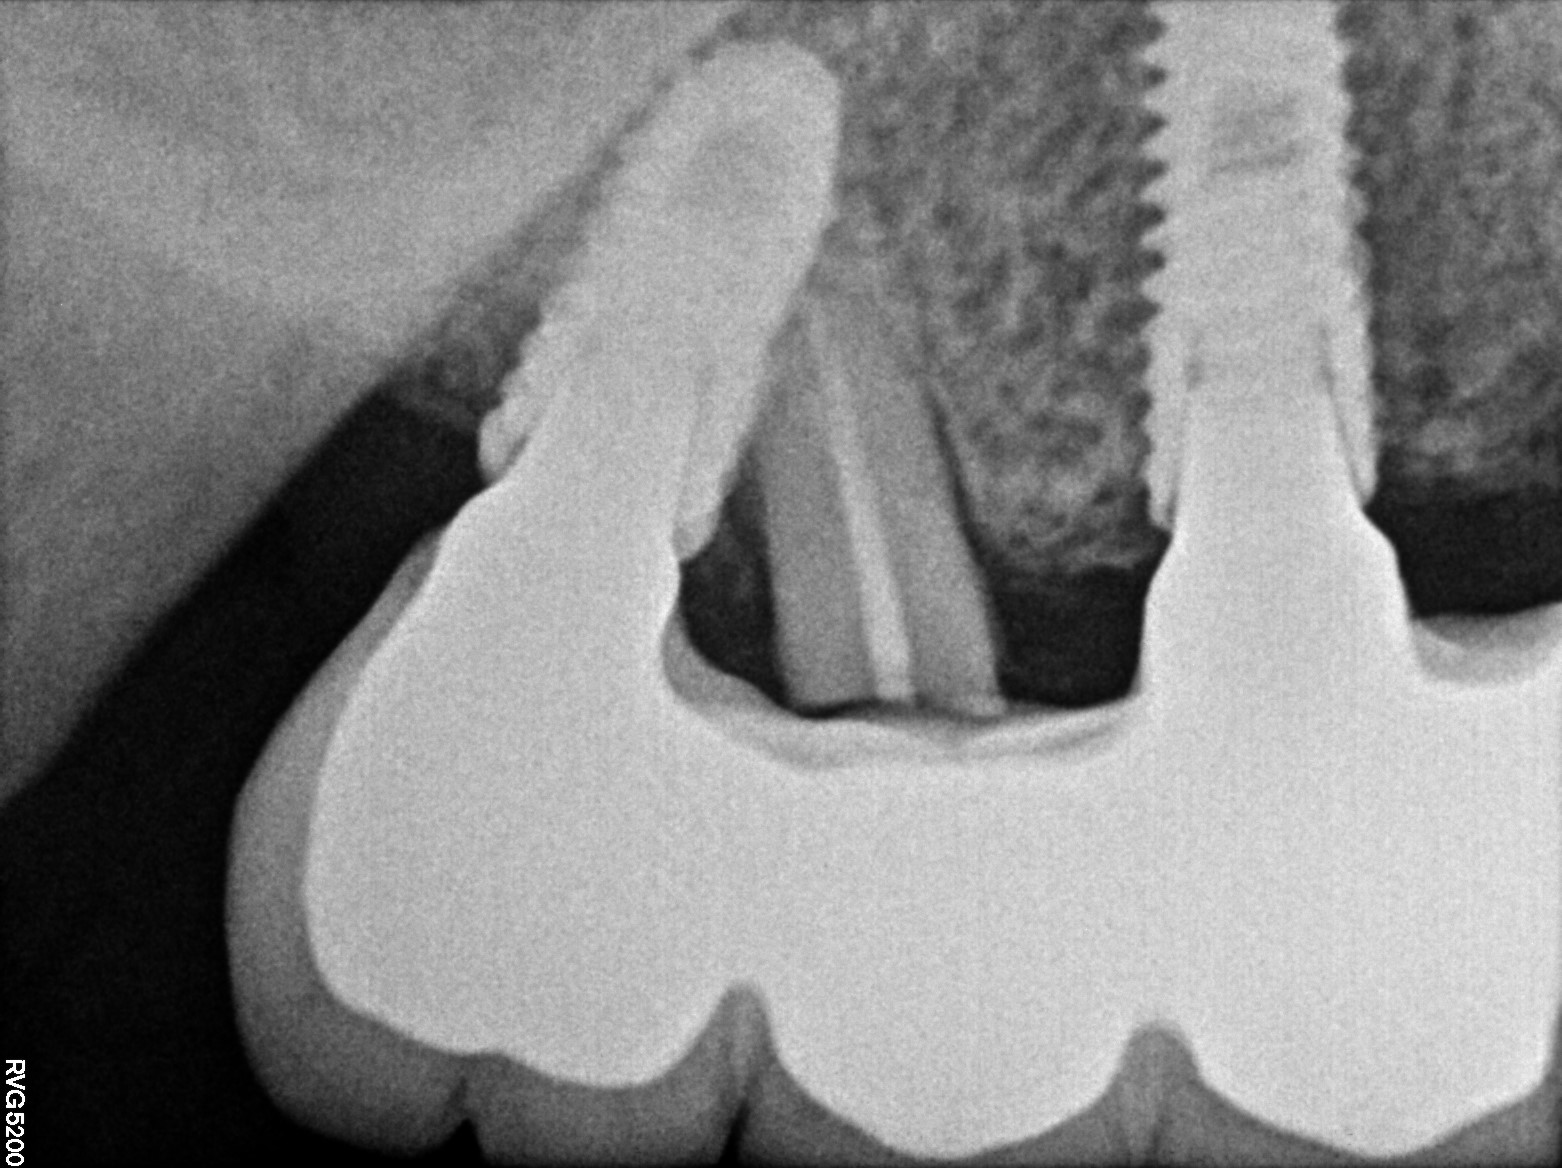

Dental Radiographs FHIR: DocumentReference · LOINC 24641-7

xray_1742374053.jpg

24641-7

| Dental implant placement | 234781005 | D6010 Surgical placement of implant body | — | 2025-03-19 | completed | full mouth implant done @ dr shoebs. came for checkup in 1st and 2nd quad. adv to return if any symptoms | |

| Dental implant placement | 234781005 | D6010 Surgical placement of implant body | — | 2025-03-19 | completed | implant hole filled |